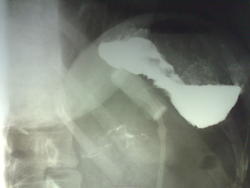

Вопрос что за тень катетера или чего то???

По ходу - это манжета, пережимающая желудок в целях поменьше жрать.

На втором скане видна вся система: порт, трубка и сама манжета. Vadim, неужели девушка не помнит, что вшила себе манжету?

Манжета и порт. Очень популярная вещь в настоящее время. Но так низко наложенную вижу впервые.

Не думаю, что изначально манжета была наложена так низко, правда, соскальзывание вниз не видела ни разу. Не совсем понятно сужение выходного отдела желудка или не все снимки показаны? Диаметр кольца манжеты не менее 3 см, вызвать сужение препилорического отдела манжета не может, тогда- что?

Но это же наружный Д, ведь мы ее в ортоградной проекции не видим...там вообще несколько мм просвет, так думаю....